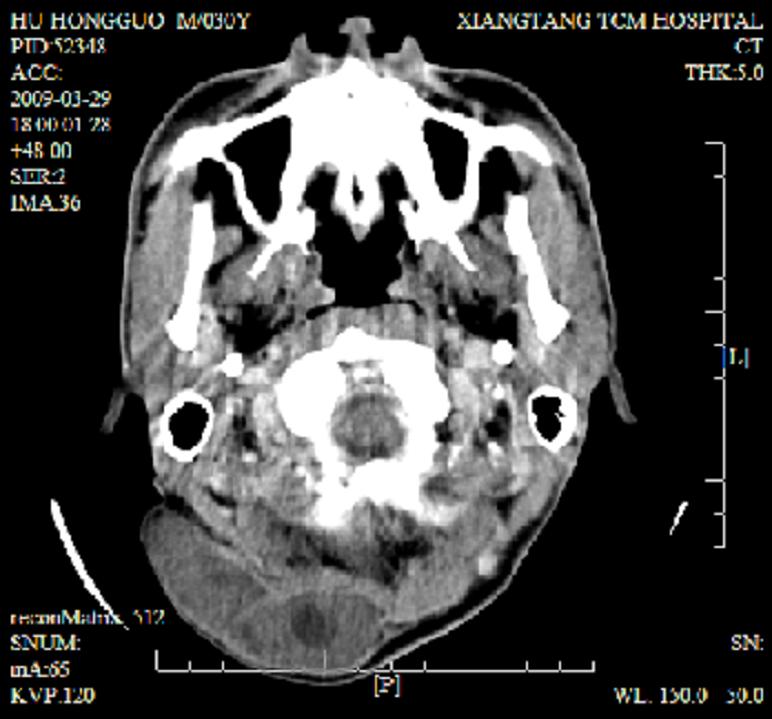

标题: CT19102:颈部肿块

男30y发现肿块3年

多处囊实性肿块,形态欠规则有一定形态,内见点状钙化,以囊变为主,增强后轻度强化,首先考虑神经源性肿瘤如鞘瘤,不除外脉管源性肿瘤如淋巴管瘤(见缝钻及囊性区域太多,如果合并感染完全可以这个影像表现),和海绵状血管瘤,但是血管瘤不太支持因为强化特征和病灶形态不典型.

右侧椎前间隙后部肌间、皮下囊性为主病变,可见分隔和点状钙化,分隔和壁呈轻度环形强化,大部分无强化。形态不规则,有钻缝特点。考虑1 淋巴管瘤合并感染2 血管平滑肌脂肪瘤3 表皮样囊肿4 不除外海绵状血管瘤。

病灶沿皮下及肌间隙爬行,病灶内有钙化灶,病灶有强化。病史3年,病人应该没什么症状。考虑纤维血管瘤可能性大。